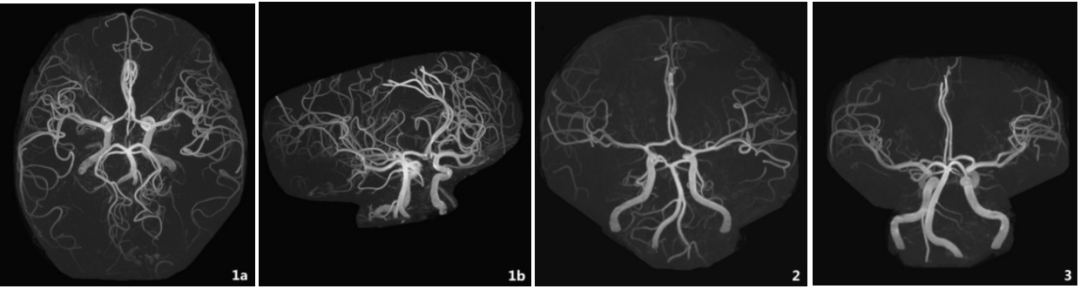

图2. 女,56岁,脑内血管显示清晰。双侧小脑上动脉起自基底动脉近终点处(A型),长度超过大脑后动脉P3段;2:女,59岁,MRA显示双侧小脑上动脉起自双侧大脑后动脉(E型);3:女,61岁,双侧小脑上动脉起自基底动脉,右侧1支,左侧2支(C型)。